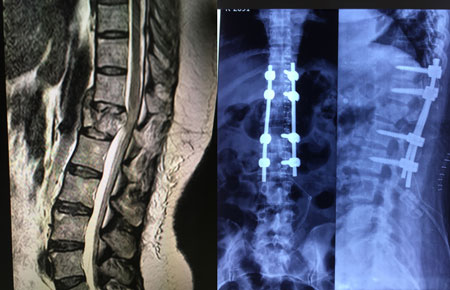

Patients with back and/or leg pain should be evaluated for issues with the back (thoracic or lumbar spine). The thoracic spine is made up of 12 vertebrae and the lumbar spine is made up of 5 vertebrae. The spinal cord runs through the middle of the thoracic spine and ends around T12-L1. The spinal canal extends down to the sacrum and houses individual nerve roots. These individual nerve roots exit the spinal canal at each lumbar level. Compression of either the spinal cord/canal or the nerve roots can result in back pain, leg pain, tingling, numbness, and/or weakness. This often occurs due to a disc herniation, stenosis (thickened ligament), or instability of the spine such as with spondylolisthesis, scoliosis, or kyphosis. Severe compression of the spinal cord in the thoracic spine can result in leg weakness and/or loss of balance.

Evaluation of back/leg pain includes a clinical exam, lumbar x-rays, MRI scan, and possibly a CT scan and/or standing scoliosis x-rays.

TLIF stands for transforaminal lumbar interbody fusion. It is a type of spinal fusion that decompresses nerves and stabilizes the spine from a posterior approach. It is usually indicated for patients with intractable back and leg pain with stenosis, disc herniation, and/or instability of the spine. Dr. Dutta specializes in minimally invasive TLIFs.

The surgeon works through the tubes to expose the bone and establish an approach to the spinal canal and nerves. He shaves the edges of the lamina and facets around the foramen (the channel where the nerve exits), thus creating the transforaminal approach to the disc space. He then decompresses the spinal canal and nerves by removing thick ligament and/or disc material that is compressing the nerves. After that, he enters into the disc and removes the disc material. He then inserts a spacer into that space, which reestablishes the height of the disc and creates a surface area for the fusion.

The surgeon then focuses on stabilizing the spine by placing screws into the bones at each level and locking the alignment in place with rods and locking nuts. The screws and rods are placed through tubes so as to preserve the muscle attachments, further contributing to the minimally invasive approach. The procedure usually takes about 2-3 hours to complete for a one level TLIF.

Posterior Instrumentation and Fusion (PSF)The goal of a posterior instrumentation and fusion is to stabilize the spine, reduce the curvature, and preserve the alignment. This is achieved with a pedicle screw and rod system, which is implanted using a minimally invasive approach. Multiple small incisions are made on the back, through which dilating tubes are placed. The screws and rods are passed through tubes so as to preserve the muscle attachments, contributing to the minimally invasive approach. The surgeon corrects the curve and alignment of the spine as he locks the rods into place. By using this minimally invasive approach, patients do not need to go to ICU, lose less blood/require fewer blood transfusions, and recover much faster, allowing them to get back to their daily activities sooner.